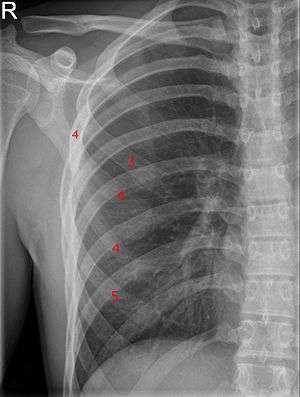

Bifid rib at the right side seen on chest radiograph. The fourth rib splits in two towards the sternal end. | |

A bifid rib (bifurcated rib or sternum bifidum) is a congenital abnormality of the rib cage and associated muscles and nerves which occurs in about 1.2% of humans. Bifid ribs occur in up to 8.4% of Samoans.[1] The sternal end of the rib is cleaved into two. It is usually unilateral.